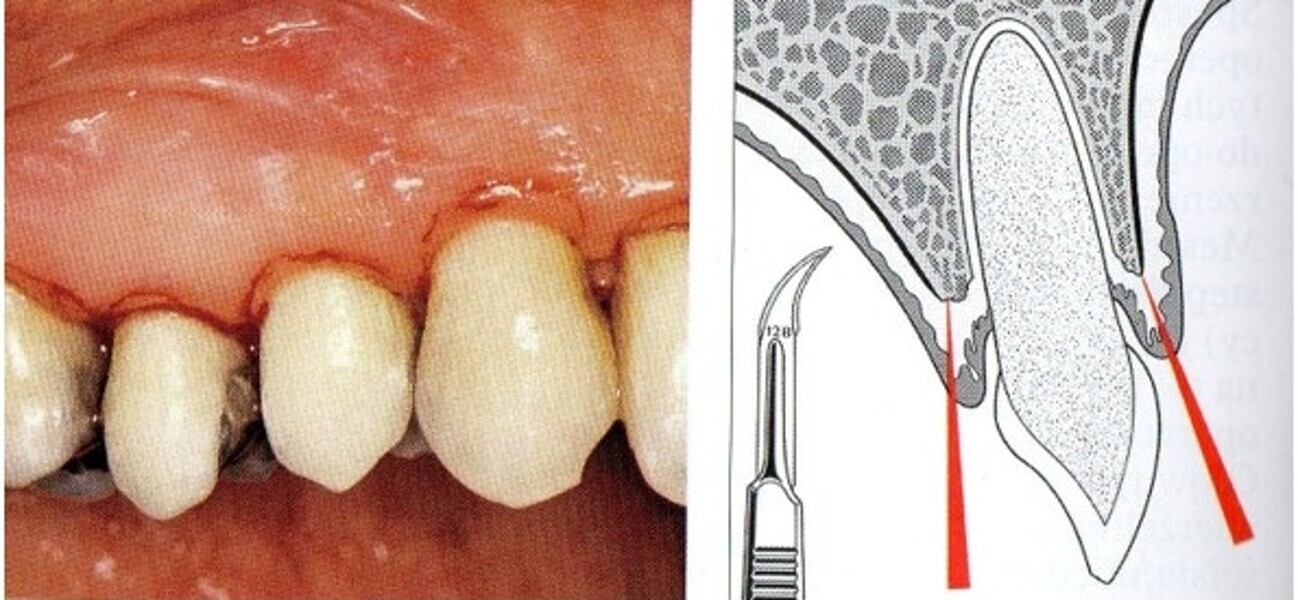

Natychmiastowa implantacja i zaopatrzenie protetyczne pacjentów z zaawansowaną chorobą przyzębia